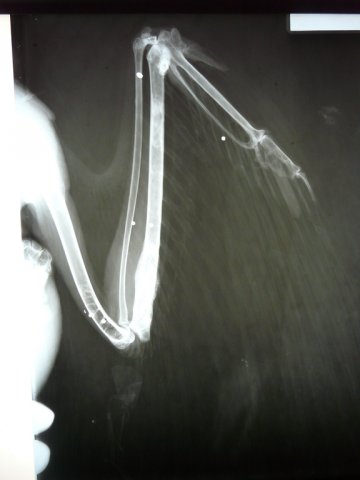

Radiografía de un águila real disparada

Detalle